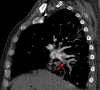

Chest CT has a potential role in the diagnosis, detection of complications, and prognostication of coronavirus disease 2019 (COVID-19). Implementation of appropriate precautionary safety measures, chest CT protocol optimization, and a standardized reporting system based on the pulmonary findings in this disease will enhance the clinical utility of chest CT. However, chest CT examinations may lead to both false-negative and false-positive results. Furthermore, the added value of chest CT in diagnostic decision making is dependent on several dynamic variables, most notably available resources (real-time reverse transcription-polymerase chain reaction [RT-PCR] tests, personal protective equipment, CT scanners, hospital and radiology personnel availability, and isolation room capacity) and the prevalence of both COVID-19 and other diseases with overlapping manifestations at chest CT. Chest CT is valuable to detect both alternative diagnoses and complications of COVID-19 (acute respiratory distress syndrome, pulmonary embolism, and heart failure), while its role for prognostication requires further investigation. The authors describe imaging and managing care of patients with COVID-19, with topics including (a) chest CT protocol, (b) chest CT findings of COVID-19 and its complications, (c) the diagnostic accuracy of chest CT and its role in diagnostic decision making and prognostication, and (d) reporting and communicating chest CT findings. The authors also review other specific topics, including the pathophysiology and clinical manifestations of COVID-19, the World Health Organization case definition, the value of performing RT-PCR tests, and the radiology department and personnel impact related to performing chest CT in COVID-19. ©RSNA, 2020.